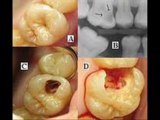

Take Care of Teeth Cavities- DDS Derek Tillman DMD

It is vital to take legitimate consideration of your teeth. On the off chance that you don’t take great consideration of them, you may lose the flavor of life. Additionally, a few genuine medical conditions are related with dental wellbeing.